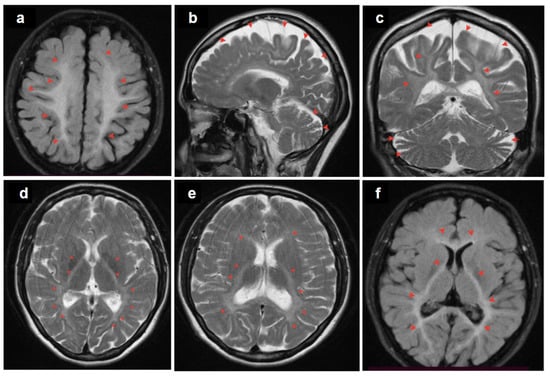

The patient was a 37-year-old woman, the only daughter of non-consanguineous parents (Figure 1). Her early development was normal. However, at the age of 35, dysarthria appeared, characterized by slow and slurred speech along with hand tremors. The condition progressed over the course of a year. Brain MRI revealed leukoencephalopathy with cortical and cerebellar atrophy (Figure 2).

Figure 2. MRI images of the brain: diffuse, bilateral hyperintensities in the subcortical white matter (a); cortical and cerebellar atrophy (b,c); coronal view of the posterior subcortical and periventricular T2 hyperintensities (c); posterior limb of the internal capsule and periventricular areas (df). Red arrows point to the affected regions.

The patient described here, a 37-year-old woman, experienced symptoms that manifested in her adulthood, such as dysarthria and hand tremors. Despite variations in age of onset and clinical features, the patient’s presentation shares similarities with patients with early manifestations, particularly regarding neurological manifestations like dysarthria, tremors, and hyperreflexia. Leukoencephalopathy with internal capsule lesions has been described earlier in VPS13D patients but is not typical for all of them (3/32 patients). The most frequent brain MRI abnormality is cerebellar atrophy (11/20) [10].

Novel cases illustrate the diverse and progressive nature of VPS13D-related disorders, which can emerge in children and adults with varying severity. Symptoms associated with VPS13D-related disorders span a broad spectrum of severity and variability, encompassing cerebellar ataxia, other movement disorder manifestations such as dystonia, chorea, and tremor, cognitive impairment, and spastic paraplegia. Additionally, reports have included chorioretinal dystrophy, seizures, hearing loss, and microcephaly [2,7,12]. Prior studies have observed symmetrical T2-weighted hyperintensities affecting the basal ganglia and brainstem, along with multifocal white matter involvement in specific patients. Furthermore, mild to moderate sensorimotor axonal polyneuropathy has been documented.